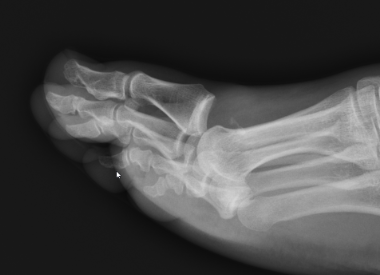

Great toe MTPJ dislocation

Pathology

Hyperdorsiflexion

Metatarsal head dislocates plantar

- tear of plantar plate / disruption bipartite sesamoid

- may buttonhole through capsule / plantar plate

Xray

Blocks to closed reduction

Capsule / plantar plate

Sesamoids

Inter-sesamoid Ligament